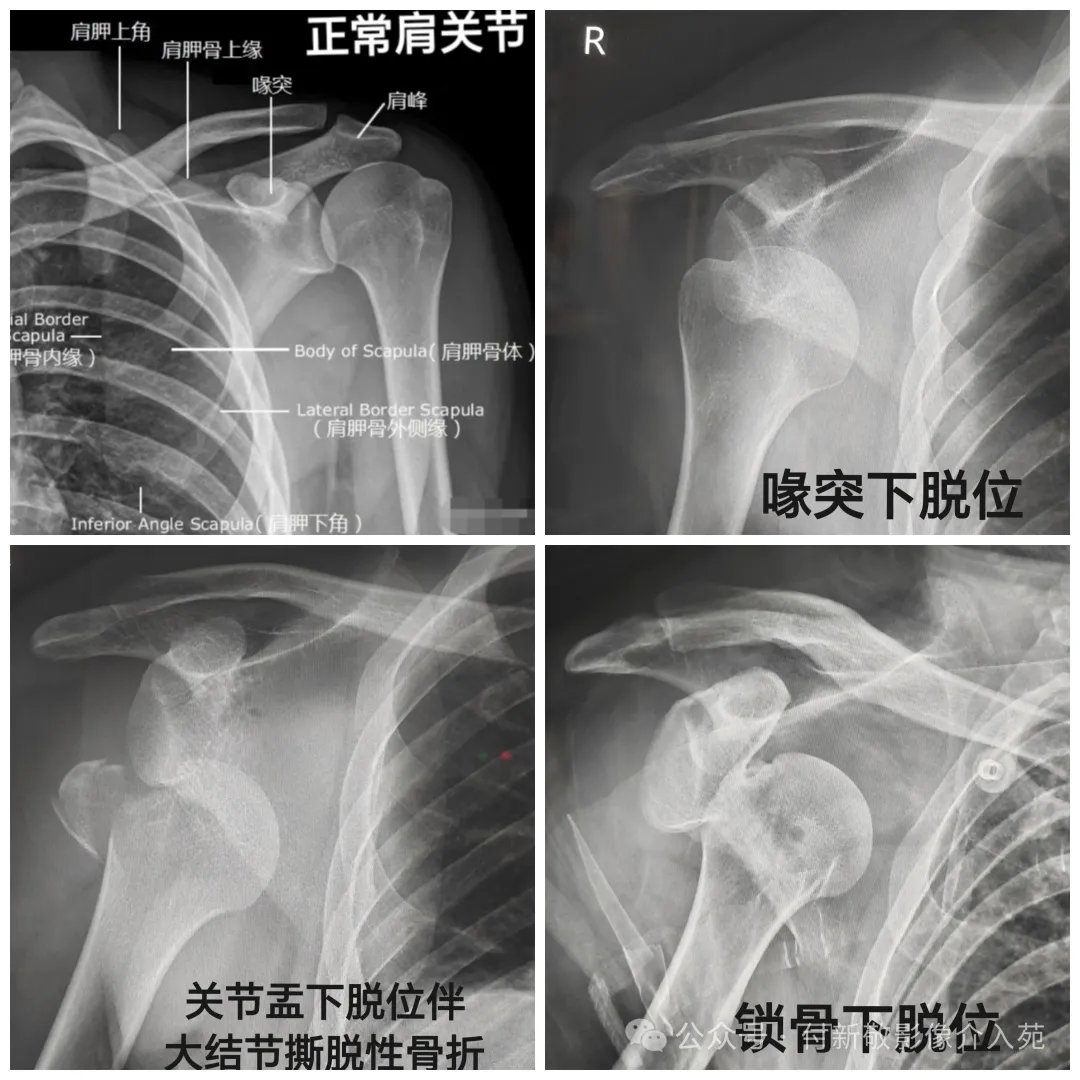

一、肩关节脱位

当我们上肢外展外旋或后伸着地的外伤时,出现肩部肿痛、不能外展,患侧出现方肩畸形,可能是肩关节脱位。

患侧肘部紧贴胸部时,手掌触不到健侧肩部,或手掌搭在健侧肩部时,肘部无法贴近胸壁,又称搭肩试验阳性,也提示肩关节脱位。

肩关节X线检查:能确诊脱位的类型,还可发现是否合并骨折。